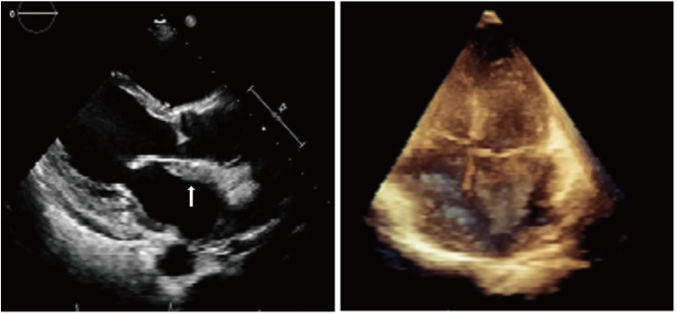

初始心电图(ECG)显示完全性房室传导阻滞(AVB)伴交界性心律(图1A)。血液检查显示肌钙蛋白水平在正常范围内,脑利钠肽前体水平为1388 pg/ml。经胸超声心动图(图2)显示整个左心房壁的左心房心内膜表面均匀等壁增厚,厚度约为1.06 cm,左心房中也观察到同样的变化。左心超声显示左房壁和左心房均匀等回声充盈,图像中无灌注。

图2. 经胸超声心动图显示整个左房壁左房心内膜表面均匀等壁增厚